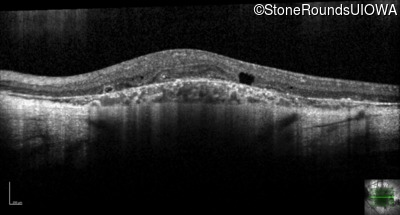

XL Choroideremia (IIIA1a)

XL Choroideremia

CHM

Deletion Exons 9-15

XL